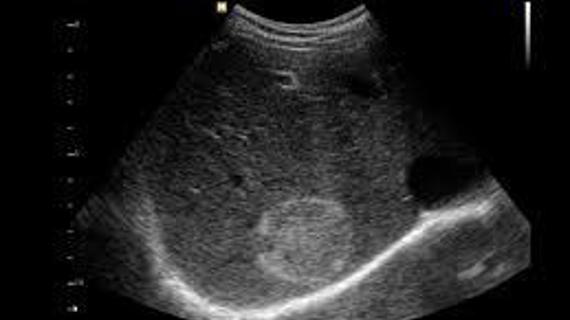

Заболевания печени